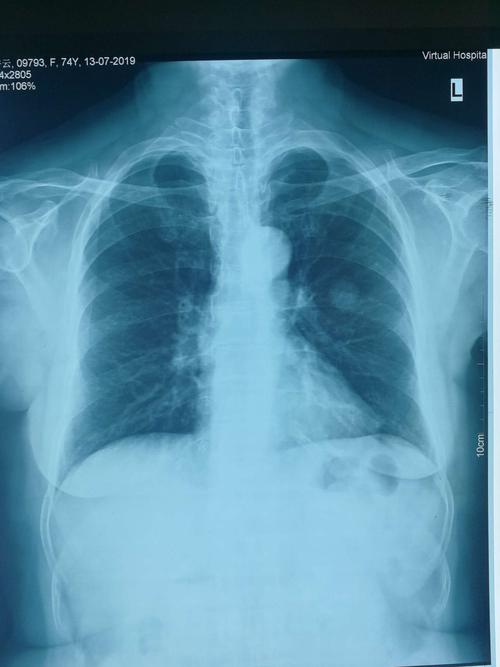

肺癌晚期 胸片

肺癌晚期 胸片,肺癌胸片晚期

某男,57岁,胸痛2月余,最近感右臂疼痛,活动受限,胸片如图,最可能的

肺癌胸片晚期

肺癌胸片

正常肺部胸片

正常胸片和异常胸片